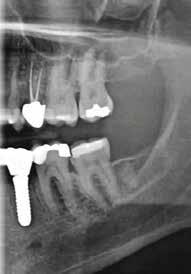

2. a–d ábra: PEEK zárócsavarok az implantátumokba helyezve, 1. eset (a). 2. eset (b). 3. eset (c), 4. eset (d). 3. a–b ábra: Röntgenfelvételek három hónap után (a) és a gyógyulási csavarok behelyezve (b, 1. eset). 4. a–b ábra: Röntgenfelvételek öt hónappal később (a) és a gyógyulási csavarok behelyezve (b, 2. eset). 2. táblázat: Az implantátum tulajdonságai.

6. a–b ábra: Röntgenfelvételek öt hónappal később (a) és a gyógyulási csavarok behelyezve (b, 4. eset).